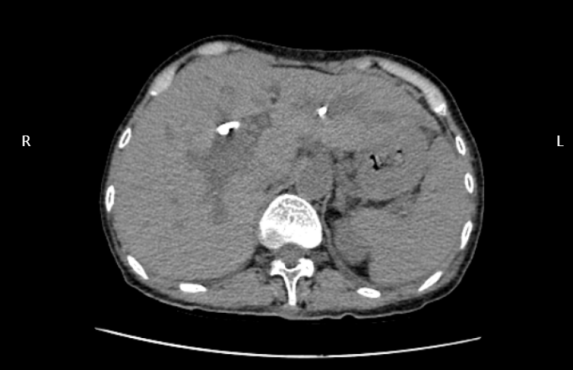

治療方案確定后,為患者實(shí)施微創(chuàng)膽道置管引流術(shù)。在床旁超聲引導(dǎo)下,成功穿刺達(dá)擴(kuò)張的膽管,置入導(dǎo)絲,引入引流導(dǎo)管,妥善固定,完成手術(shù)。手術(shù)過(guò)程中,患者生命體征平穩(wěn),穿刺置管順利,達(dá)到預(yù)期目的。

術(shù)后CT顯示引流管準(zhǔn)確置入擴(kuò)張的膽管